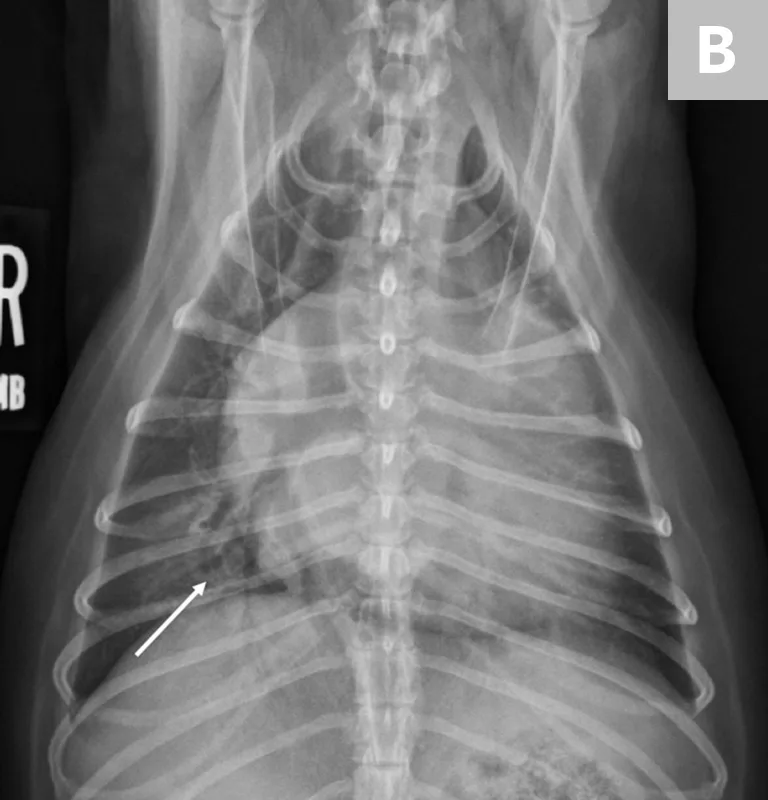

In cats, a ventral or diffuse interstitial-to-alveolar pattern may be present3,5; pleural effusion is indicated by pleural fissure lines, retraction of the lung lobes, and effacement of the cardiac silhouette.6 (See Figure 2.) Dyspneic cats with evidence of pulmonary infiltrates should receive a presumptive diagnosis of cardiogenic pulmonary edema until proven otherwise (often by a clinical diuretic trial).

FIGURE 2

L-CHF in a cat with cardiomegaly and pleural effusion with visible pleural fissure line (arrow).